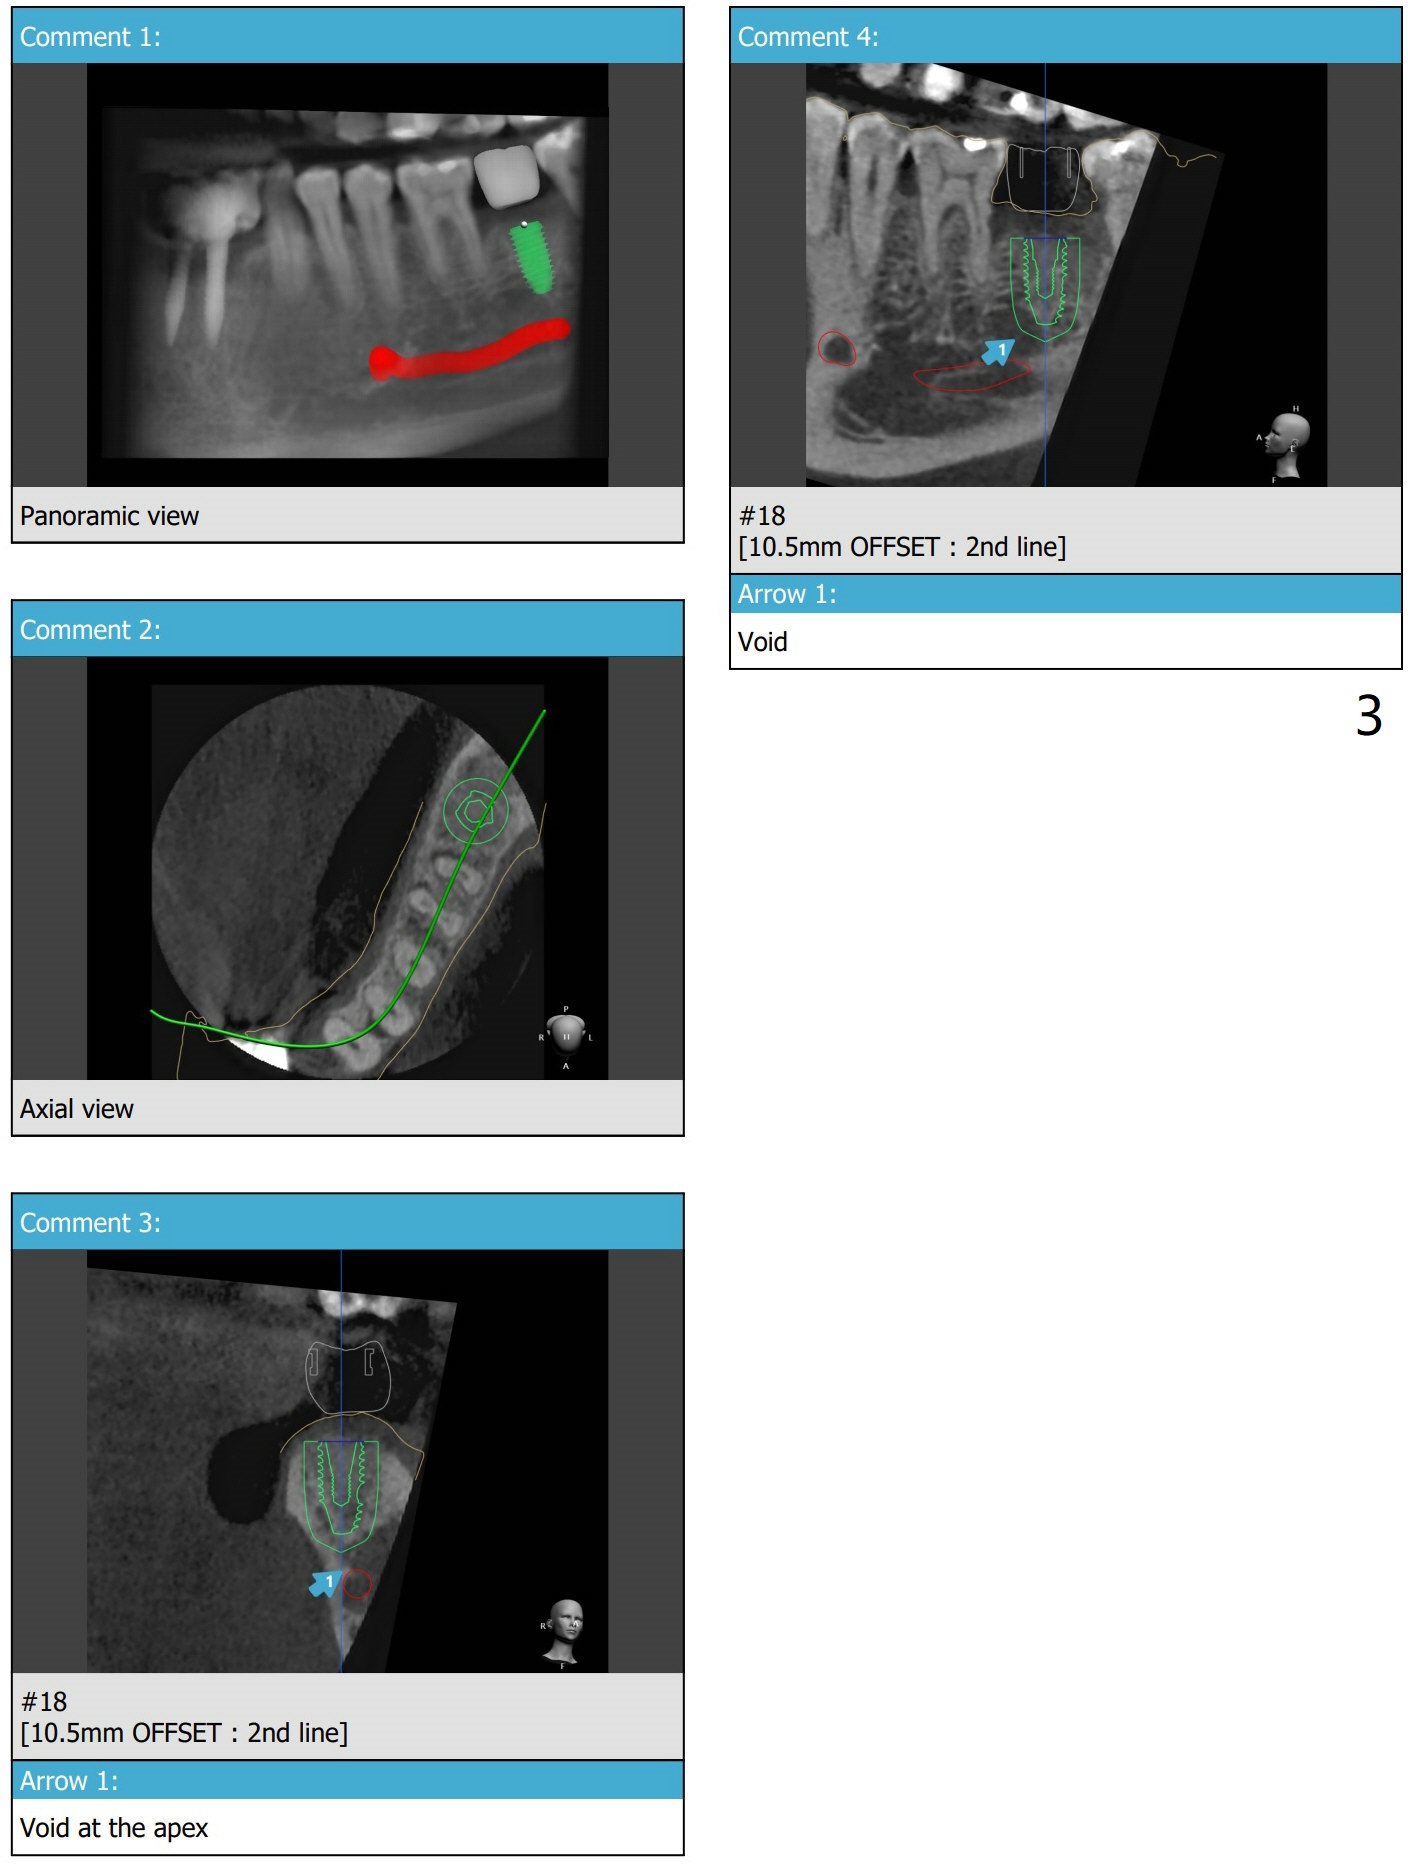

植体周围骨缺损

完成钻洞后,检查近中颊侧缺损,必要时植骨,收集钻头上的骨粉